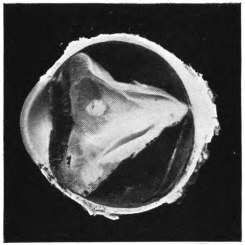

PLATE III.

16.

ABUNDANT EXUDATE INTO VITREOUS CAVITY

curly bracket span

42

17.

LENS FIRMLY FIXED BY ORGANIZED EXUDATE

18.

LENS FIRMLY FIXED BY ORGANIZED EXUDATE, BUT IN UNUSUAL POSITION

19.

TOTAL DETACHMENT OF RETINA, WITH CYST FORMATION

20.

RECLINED LENS LYING IN FRONT OF THE HYALOID BODY

21.

RECLINED LENS LYING IN FRONT OF THE HYALOID BODYxii